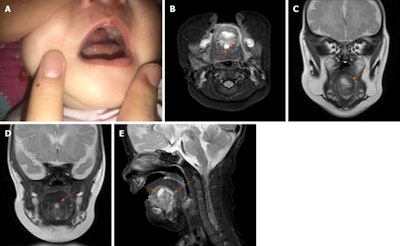

At week 24 of the mother's pregnancy, the lesion was 1.9 x 1.8 cm. By week 34, it had grown to 2 x 3 cm. At birth, the cyst had grown to nearly fill the patient's oral cavity. Gradually, it affected her breathing and her ability to swallow. At 1 month old, the otherwise healthy girl was taken to the hospital for swelling and dysphasia. The baby could not close her mouth. An MRI revealed a 3.3 x 2.8 x 2.9-cm cystic lesion, pushing the baby's tongue backward, according to the authors.

A week later, an MRI scan of the tongue revealed two small cystic lesions under the infant's tongue. One was about 0.8 x 1 x 0.5 cm, and the other was 1.2 x 0.5 x 0.5 cm. After reviewing the preoperative MRI, doctors identified a suspicious lesion of minute size that they believe they missed due to the larger cyst compressing it and doctors focusing on the most pronounced findings on the scan. After the sizable cyst was removed, the missed one grew rapidly. Nine days after surgery, the patient was discharged. An exam of the removed cyst showed it was a keratinizing stratified squamous epithelial lining complete with sebaceous adnexa, confirming it was a dermoid cyst, the authors wrote.